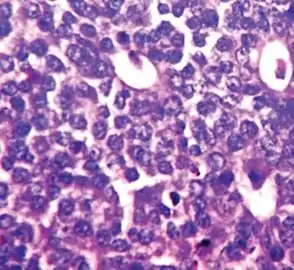

Mitotic count

Mitosis appearances in breast cancer

This parameter assesses how many mitotic figures (dividing cells) the pathologist sees in 10x high power microscope field. One of the hallmarks of cancer is that cells divide uncontrollably. The more cells that are dividing, the worse the cancer.

Note: Mitotic figures are counted only at the periphery of the tumor, and counting should begin in the most mitotically active areas.